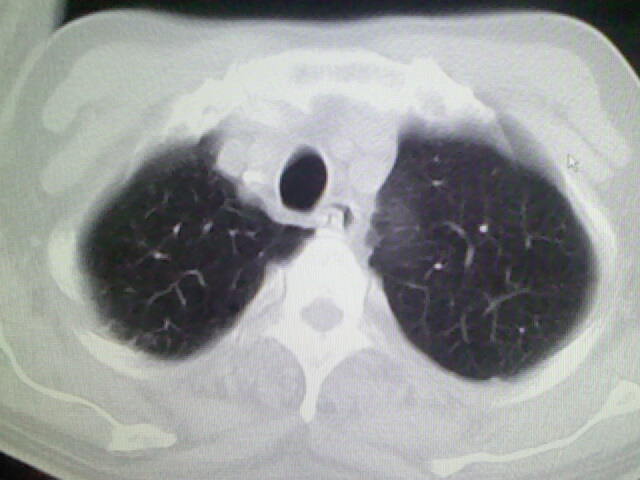

男,70岁,脑出血,长期卧床,左侧背部可触及肿块

右肺病灶考虑炎症性。

右肺病灶考虑炎症性

考虑右肺及左肺下叶炎症。

考虑右肺及左肺下叶慢性炎症。